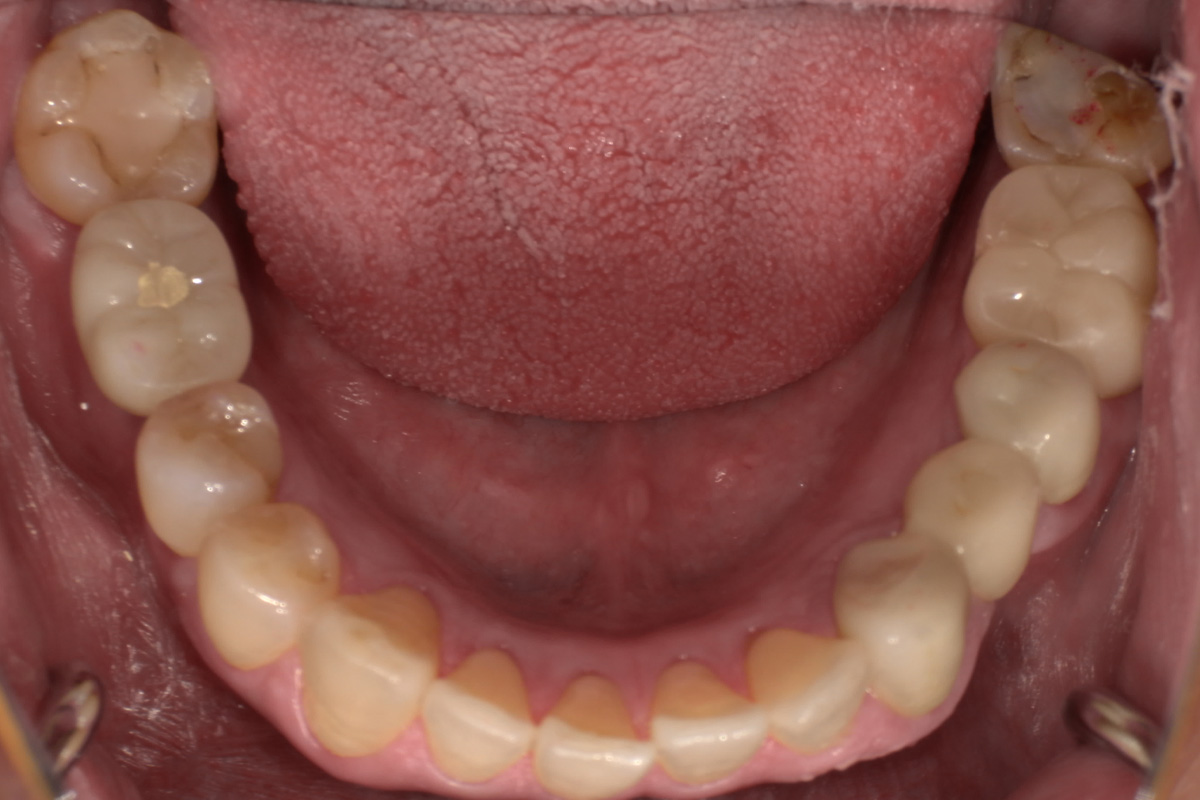

初診時

歯が割れていて、痛みがあり、抜歯となりました。

レントゲン画像 治療前 インプラント治療後